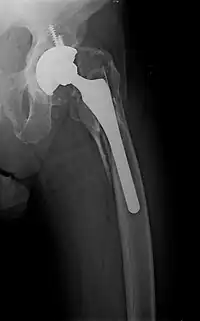

- Periprosthetic fracture – a fracture at the point of mechanical weakness at the end of an implant.

Surgical methods of treating fractures have their own risks and benefits, but usually, surgery is performed only if conservative treatment has failed, is very likely to fail, or is likely to result in a poor functional outcome.[42] With some fractures such as hip fractures (usually caused by osteoporosis), surgery is offered routinely because non-operative treatment results in prolonged immobilisation, which commonly results in complications including chest infections, pressure sores, deconditioning, deep vein thrombosis (DVT), and pulmonary embolism, which are more dangerous than surgery.[43] When a joint surface is damaged by a fracture, surgery is also commonly recommended to make an accurate anatomical reduction and restore the smoothness of the joint.

Sometimes bones are reinforced with metal.[45] These implants must be designed and installed with care. Stress shielding occurs when plates or screws carry too large of a portion of the bone's load, causing atrophy. This problem is reduced, but not eliminated, by the use of low-modulus materials, including titanium and its alloys. The heat generated by the friction of installing hardware can accumulate easily and damage bone tissue, reducing the strength of the connections. If dissimilar metals are installed in contact with one another (i.e., a titanium plate with cobalt-chromium alloy or stainless steel screws), galvanic corrosion will result. The metal ions produced can damage the bone locally and may cause systemic effects as well.